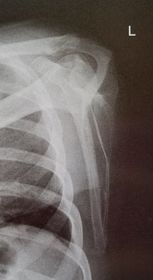

| AP Shoulder internal rotation | the MCP is tilted posteriorly as marked by the superior scapular angle is inferior to the clavicle |

| AP Shoulder | patient is rotated towards the unaffected shoulder: decreased thoracic superimposition over the scapular body |

| AP Shoulder | patient is rotated towards affected side:increased thoracic superimposition over the scapular body |

| AP Shoulder Neutral | ANATOMY: proximal humerus, lateral 2/3 of clavicle, open shoulder joint CRITERIA: humeral epicondyles are 45 degrees to the IR neither tubercle should be seen on the humeral head POSITIONING: CR perpendicular @ 1'' inferior to coracoid process |

| AP Shoulder Internal Rotation | CRITERIA: lesser tubercle in profile medially POSITIONING: CR perpendicular @ 1'' inferior to coracoid process |

| AP Shoulder External Rotation | CRITERIA: greater tubercle in profile laterally POSITIONING: CR perpendicular @ 1'' inferior to coracoid process |